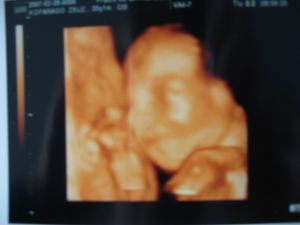

Ó, NAGYON ÉDES MÁRTONKA ÁM, NAGYON TETSZIK!!! NÁLUNK ITT DEBRECENBEN 11000FT A 4D UH, ÉS AZT MONDTÁK, HOGY A 25-28.HÉTEN A LEGSZEBB A BÉBI, ÍGY AZ ENYIM MÉG VÁRAT MAGÁRA.DE ÚGY KEDVET KAPTAM, MERT A TIEITEK IS OLYAN SZÉPEK, (A BÉBIK IS, MEG A FELVÉTEL MINŐSÉGE IS), HOGY ESTE MEGFŰZÖM APÁT, HOGY ELŐBB MEHESSEK A NYUSZIVAL.SZURKOLJATOK, HOGY SIKERÜLJÖN, JÓ?

Kispiskóta: annira jó ez a kép. Kis vigyori! Éééééédes!

Kispiskóta: Odabújik, és mosolyog....ugye látjátok? Egyszerűen gyönyörű:)